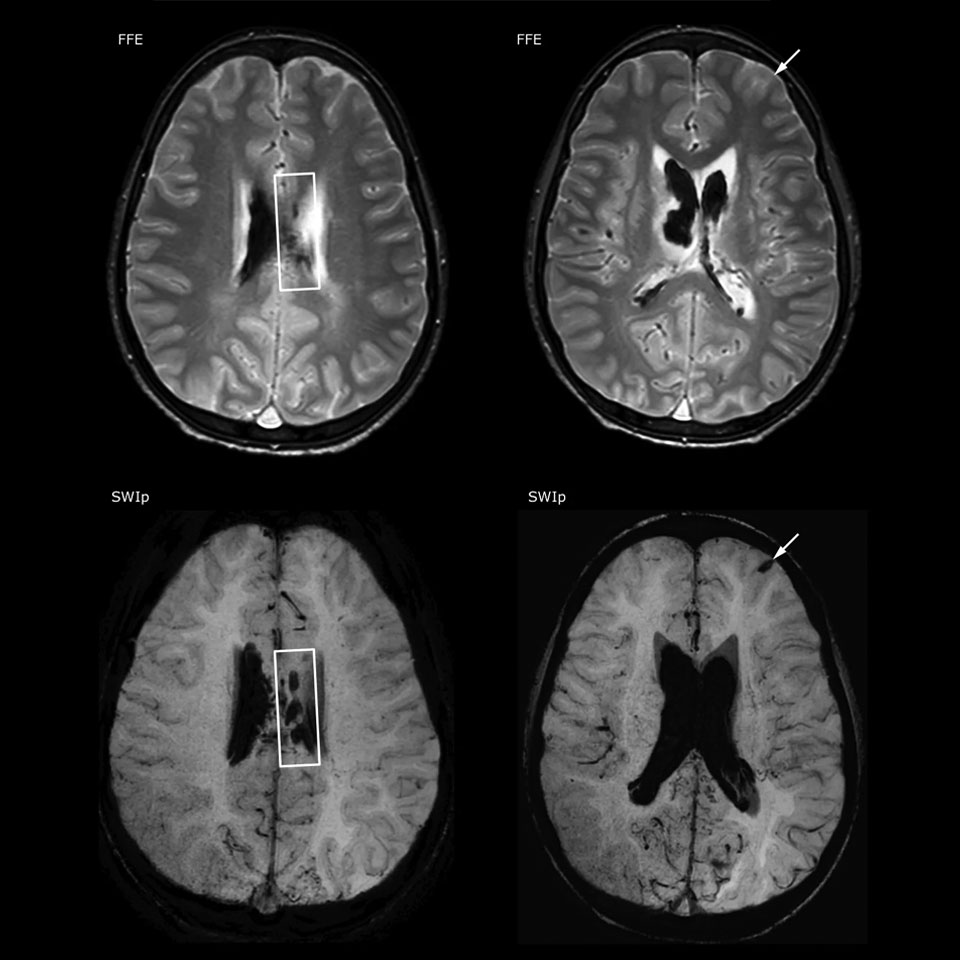

The value of susceptibility weighted imaging in visualizing brain injury is well documented. The Philips multi-echo SWIp technique provides fast susceptibility weighted imaging with enhanced susceptibility contrast and high resolution.

“Pediatric imaging is not without its challenges,” Dr. Miller says. “Since our patients are often very small, we need very high-resolution imaging. In cases of brain injury, we need to obtain information quickly so the treating clinicians can make decisions on care. We rely on high resolution and robust imaging capabilities, and SWIp provides that.”

“SWIp helps us identify blood or blood products, calcification, and diseases that affect the vascular system,” says Dr. Miller. “In children with traumatic brain injuries, it highlights areas that are injured, better than some of the previous techniques that we were using. These children often have micro-injuries that cause small amounts of blood or tissue damage. Adding SWIp helps us to better characterize the extent and nature of the injury. Having characterized an injury to the extent of what’s possible supports our diagnostic confidence.”

“I would definitely recommend other users to implement SWIp. We initially added the SWIp sequence following a lot of support for its utility in the literature. Then we directly compared SWIp to the 2D gradient echo sequences that we were using. After a good amount of clinical experience in seeing its benefits, we were confident to replace the old sequences with SWIp. It gives us a better assessment of the physiological processes of the brain that were less apparent on our previous imaging sequences,” says Dr. Miller. “SWIp is now a routine sequence for imaging traumatic brain injury patients at PCH, and it’s episodically added for patients who have intracranial vascular abnormalities.”

“I believe SWIp is rapidly becoming the standard in imaging traumatic brain injury, because of its high sensitivity to venous blood products. SWIp may even help attract patients; our neurosurgeons often ask to have the patients imaged on our scanners with highly sensitive techniques like SWIp. There’s also a growing application of SWI sequences in other vascular abnormalities because of the possibilities around physiological assessment of the brain than just a standard structural imaging.”